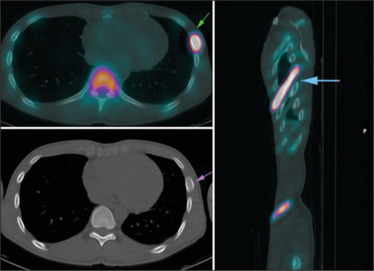

患者,37岁男性,最初表现为直肠出血。结肠镜检查显示直肠下部有圆周性病变,并伴有少量卫星性病变。当时,我们进行了活检,但组织病理学检查显示一致的孤立性直肠溃疡综合征。随后的骨扫描显示左侧第6肋骨的放射性示踪剂摄取增加,导致相应的单光子发射计算机断层扫描(SPECT)显示“香蕉样外观”和磨砂玻璃外观,与纤维发育不良相一致。鉴于其无症状状态,患者接受了关于其良性骨病变的安慰和监测。

The patient, a 37-year-old male, initially presented with per rectal bleed. Colonoscopy revealed a circumferential lesion within the lower rectum, along with a few satellite lesions. At that time, we performed a biopsy, but the histopathological examination revealed consistent solitary rectal ulcer syndrome. Subsequent bone scan revealed increased radiotracer uptake at the left 6th rib, resulting in a "banana-like appearance" and a ground glass appearance on the corresponding single-photon emission computed tomography (SPECT), in keeping with fibrous dysplasia. Given his asymptomatic state, the patient received reassurance and surveillance regarding his benign bone lesion.